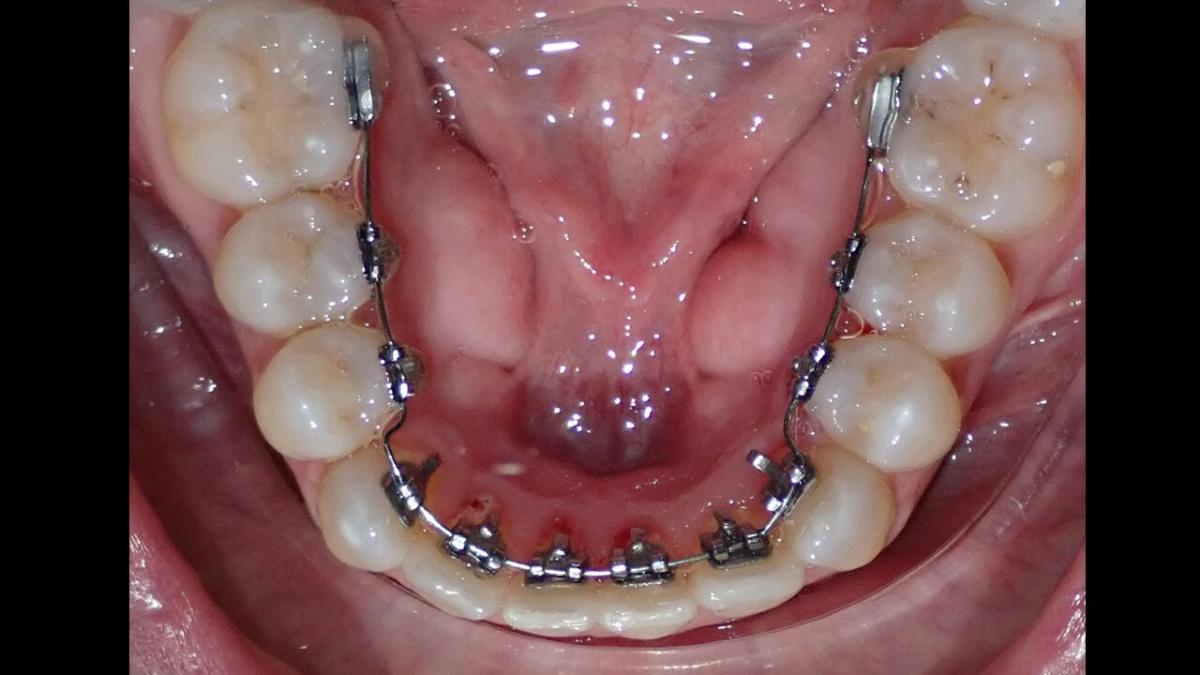

large-Ortodoncia Lingual

large-Ortodoncia lingual invisible

large-Lingual